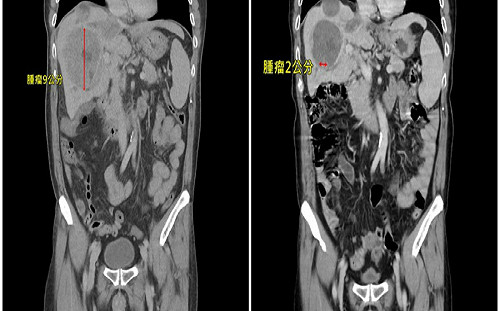

男患肝癌轉移「肺部佈滿數十顆腫瘤」 用對療法僅剩兩顆